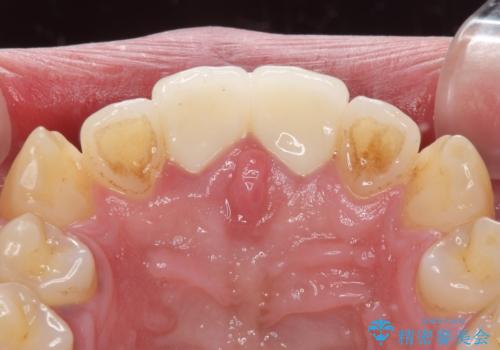

1度の来院で進められる限りの処置を行ったため、4回の来院で僅か1ヶ月で治療を終えることができました。

気になっていた前歯の問題が解決し、患者様には大変満足していただきました。